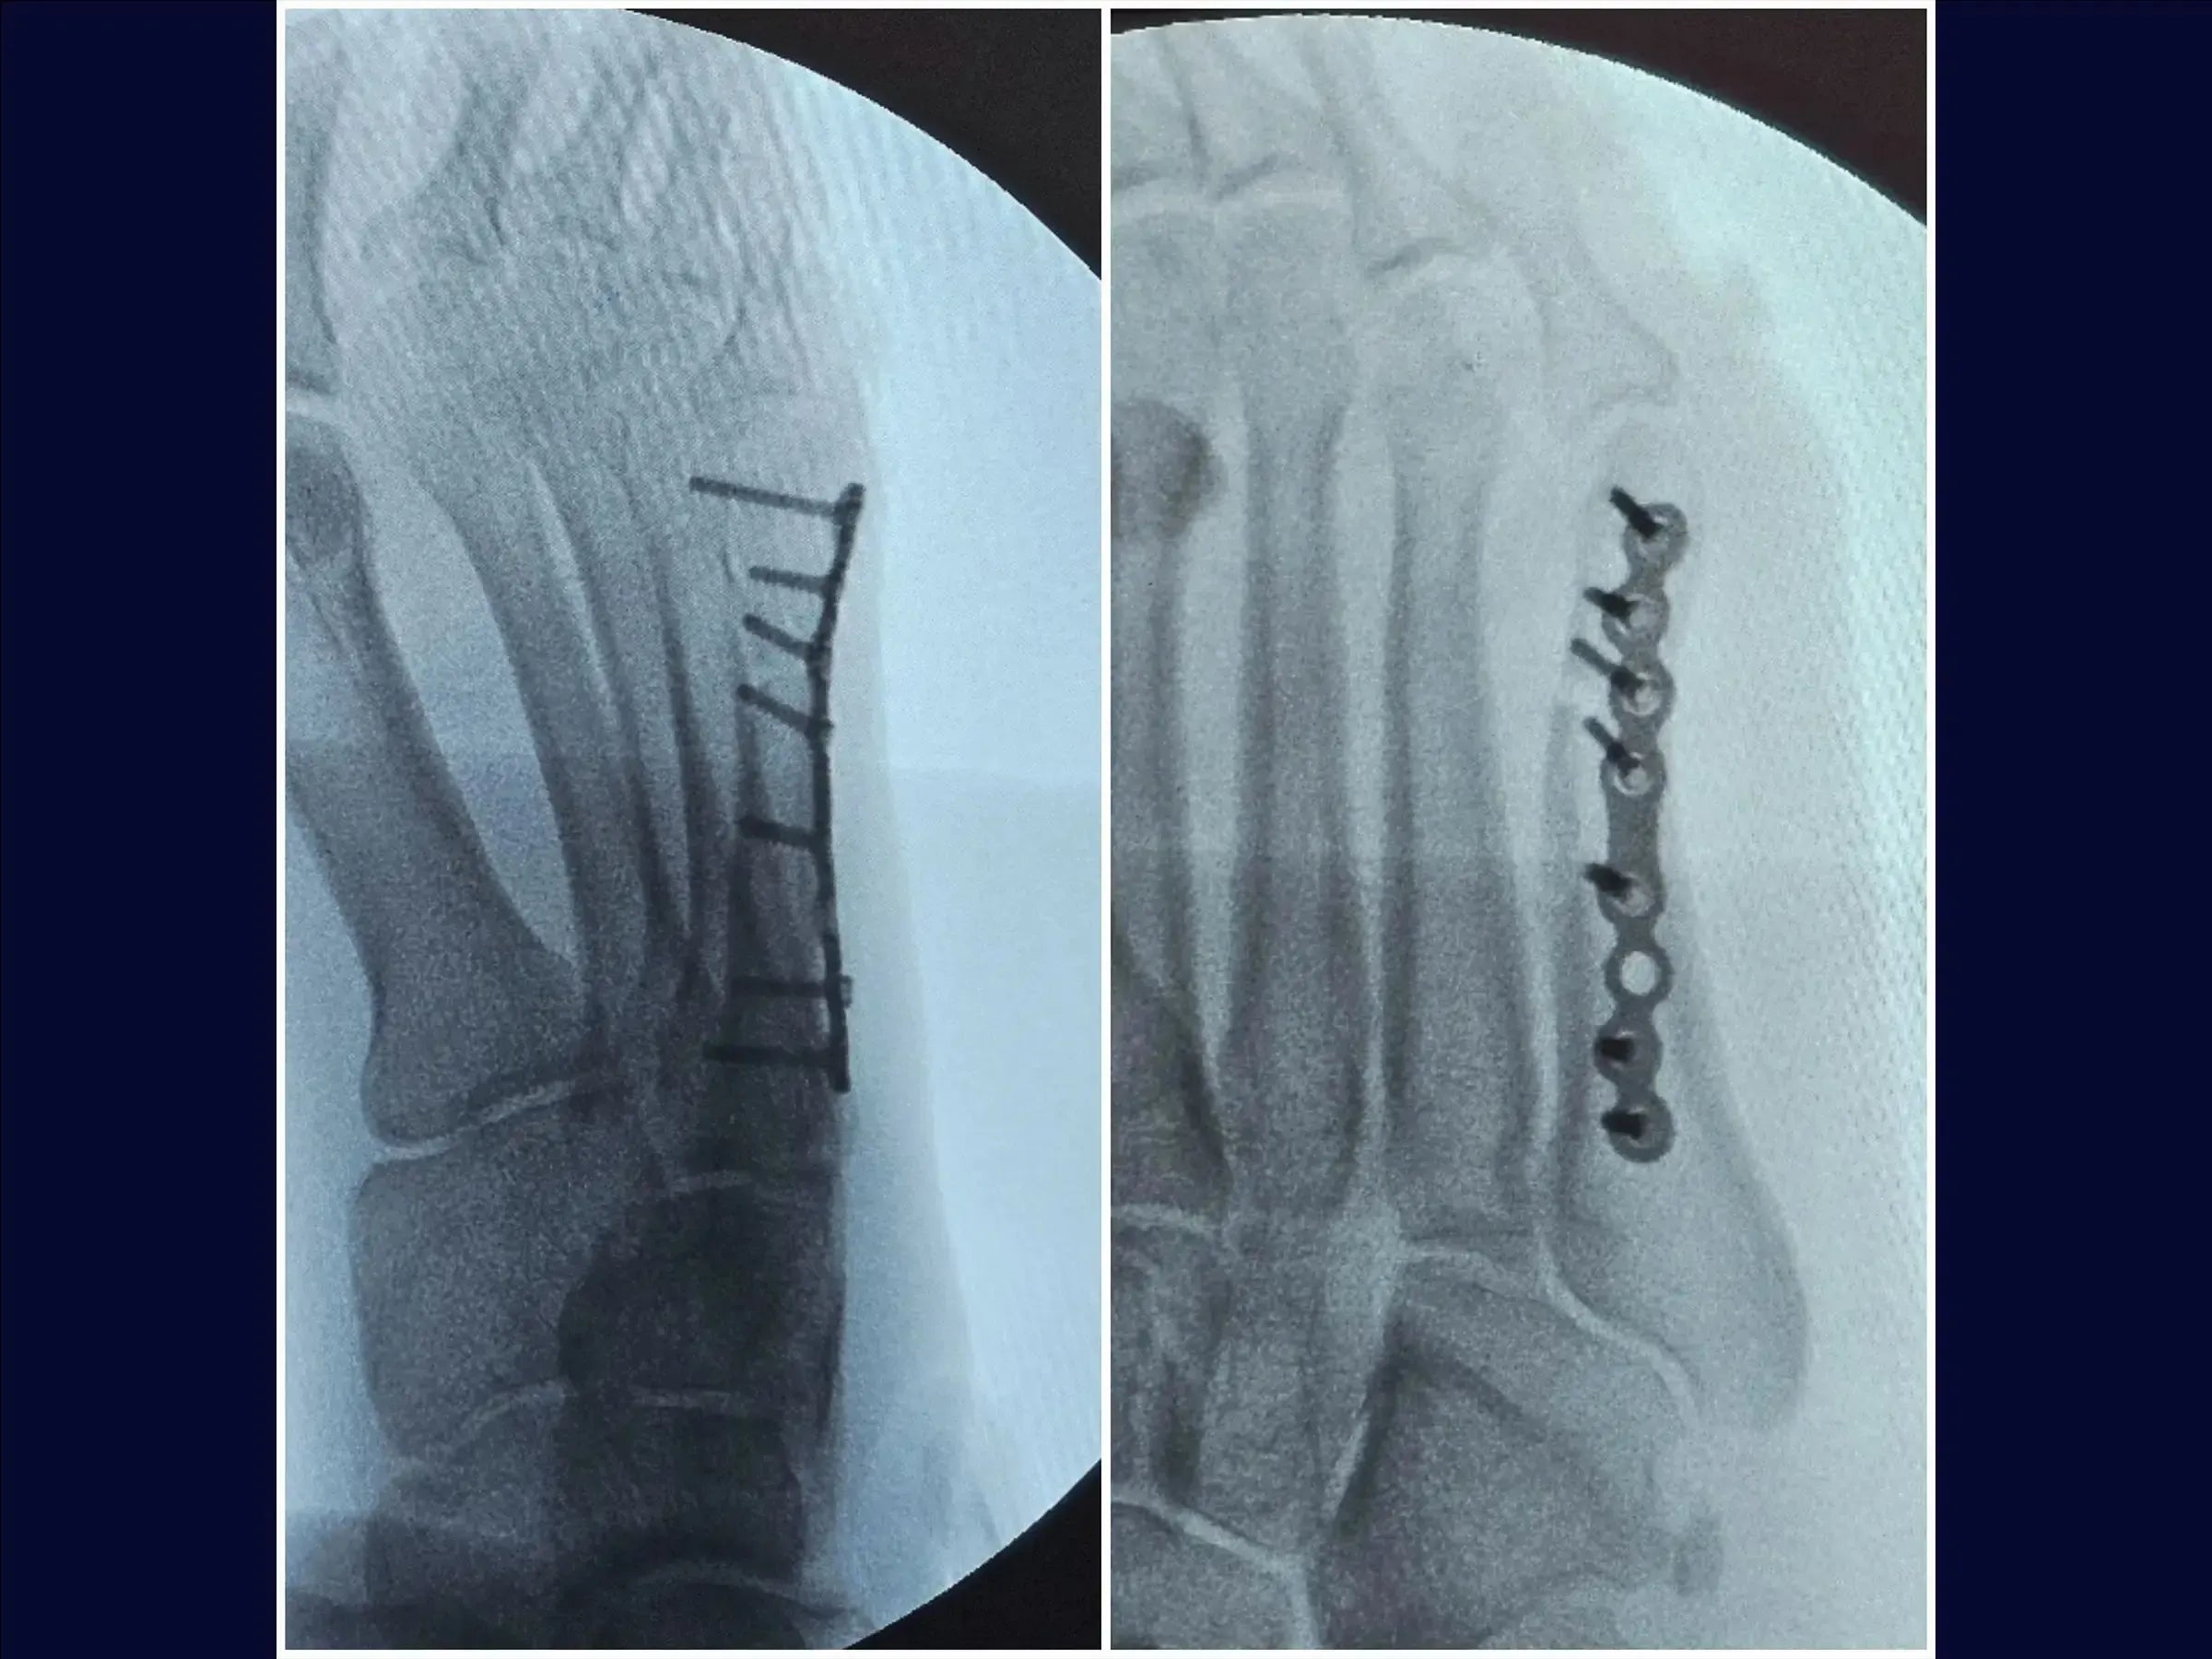

Mejore sus habilidades en el tratamiento quirúrgico de fracturas desplazadas del quinto metatarsiano. Este procedimiento requiere una reducción anatómica cuidadosa para evitar la metatarsalgia o la disfunción de la marcha, especialmente en pacientes jóvenes y atletas. Esta capacitación detalla el procedimiento quirúrgico con placa de bloqueo y tornillos, con énfasis en la rápida recuperación funcional y el retorno a la actividad deportiva.

- Reducción anatómica y fijación estable con placa de bloqueo.

- Reducción de la fractura y estabilización provisional: Identificación de los vértices de la fractura, reducción bajo visualización directa con pinza de reducción y estabilización provisional con agujas de Kirschner, evitando la zona de la futura placa.

- Fijación Definitiva con Placa Bloqueada: Colocación de una placa minifragmentaria de perfil bajo, utilización de tornillos largos para una adecuada distribución de la carga y reducción de la necesidad de futuras extracciones.

- Cierre y resultados: Cierre plano, con demarcaciones para resultados estéticos. La fijación estable permite la carga temprana con calzado de suela rígida.